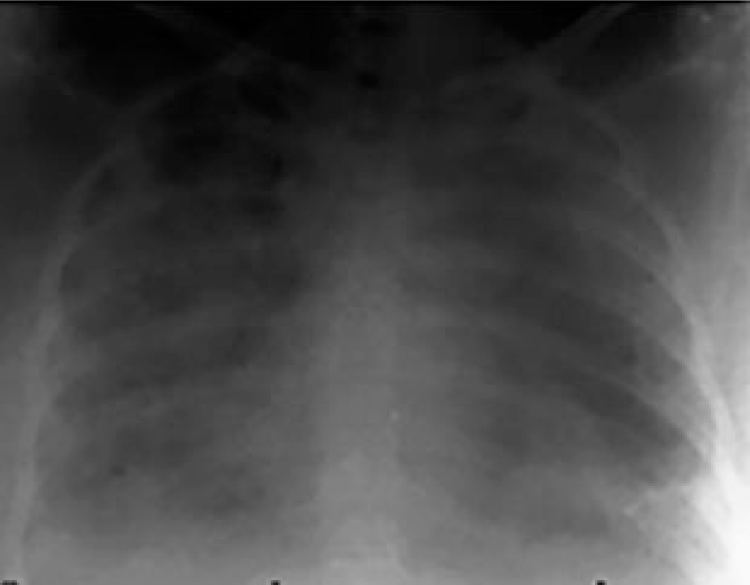

A pulmonary edema is characterized by an accumulation of fluid in the interstitium of the lung tissue and / or the alveoli. This leads to impaired gas exchange and may even cause pulmonary failure. The amount of the pulmonary edema can easily be quantified at the bedside by measuring the extravascular lung water index (ELWI). The usual clinical signs of pulmonary edema (white-out on the chest X-ray, low oxygenation index, decreased lung compliance) are non-specific and only indicative when the edema is at an advanced stage. In the critical care routine, the chest X-ray is often used to estimate pulmonary edema in patients at risk. This approach is imperfect as the chest X-ray provides only a black and white density image of all components in the chest, including gas volume, blood volume, pleural effusion, bones, muscles, lung tissue, fat, skin edema and also pulmonary edema.[1]

ELWI = 21 ml/kg

Severe pulmonary edema